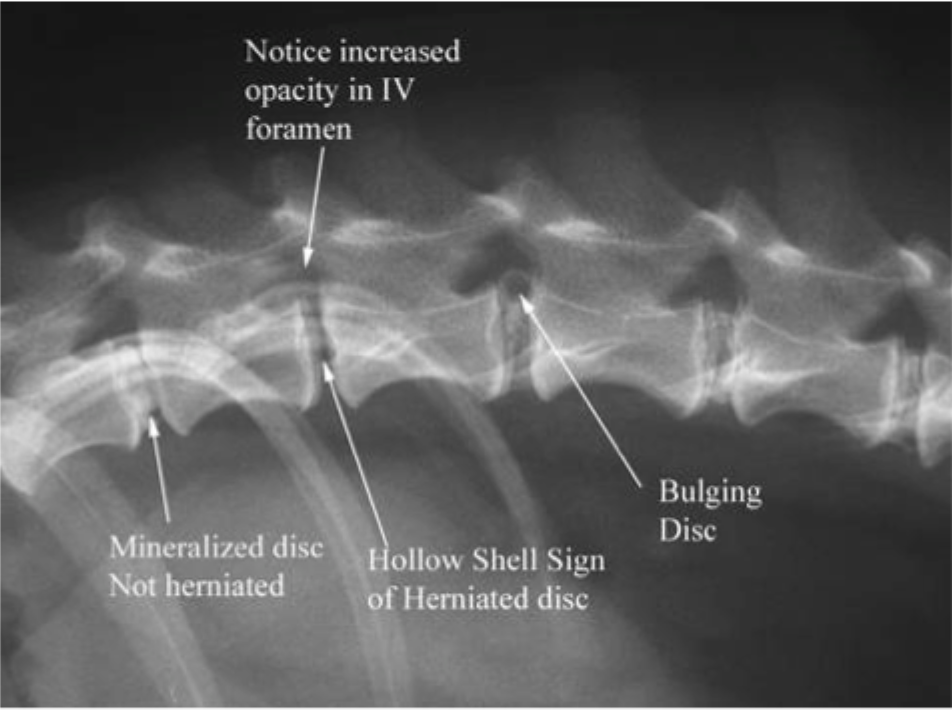

Name the condition: a prolapse of intervertebral discs with subsequent neurological signs

IVDD

• Intervertebral disc disease

• Annulus fibrosis ruptures

• disc gets pushed into the spinal cord (neurologic symptoms)